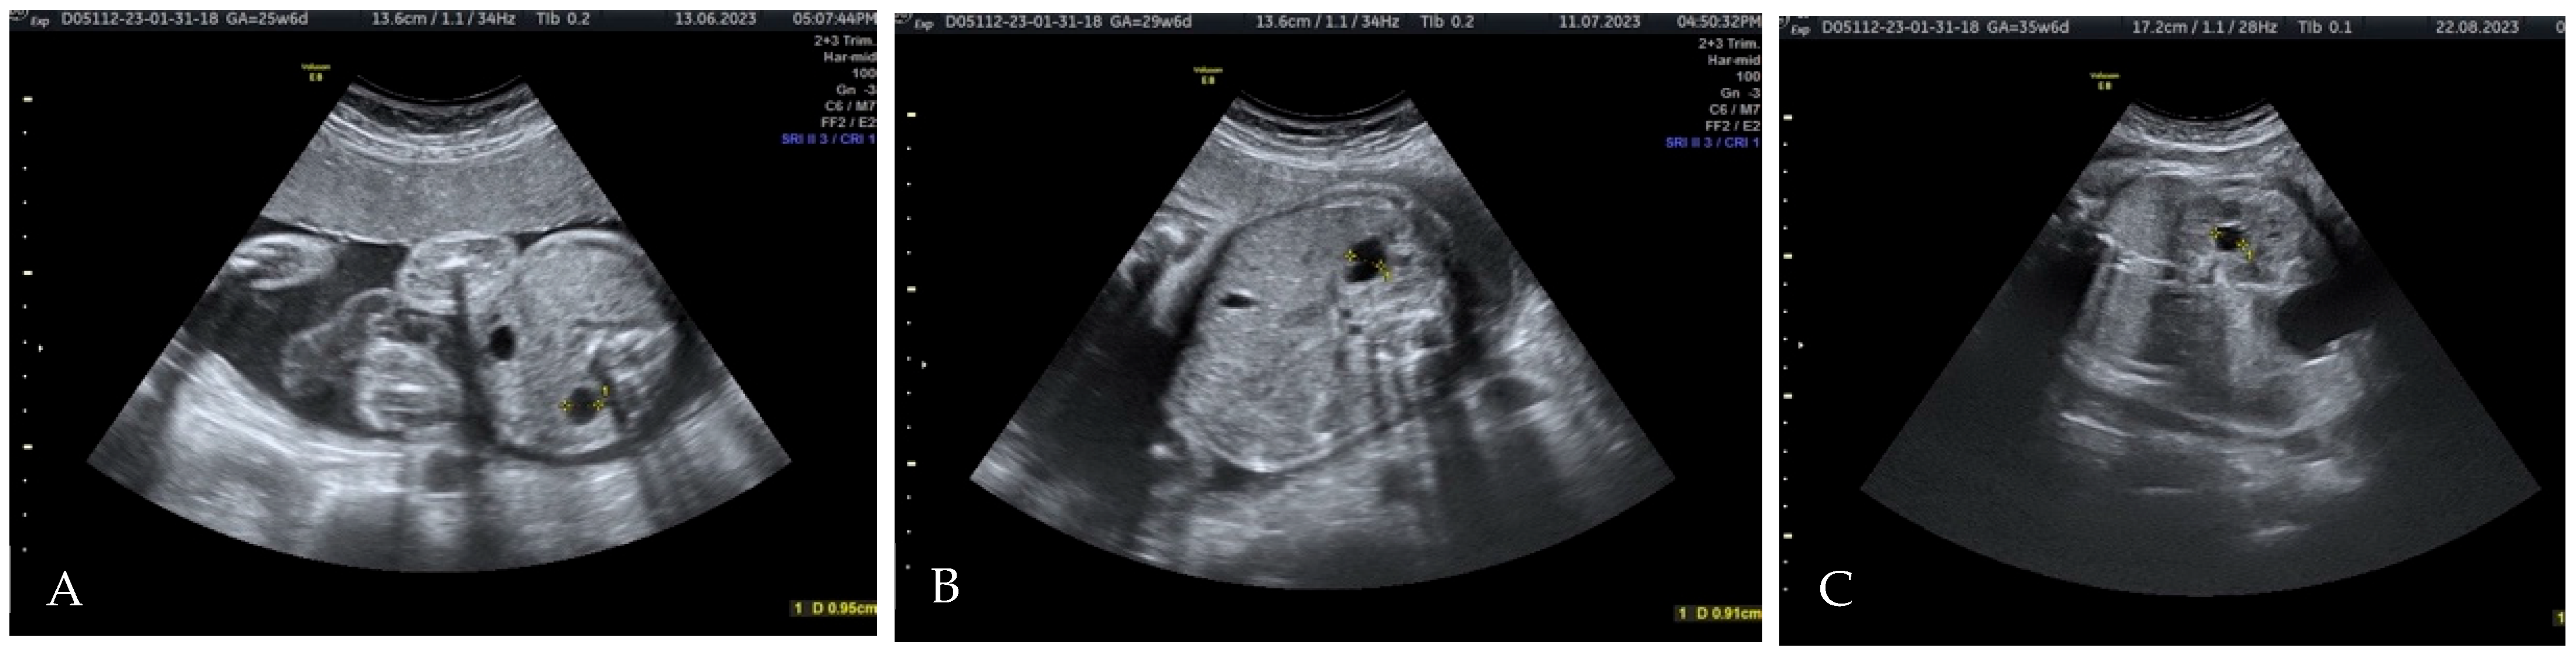

2. Case Presentation